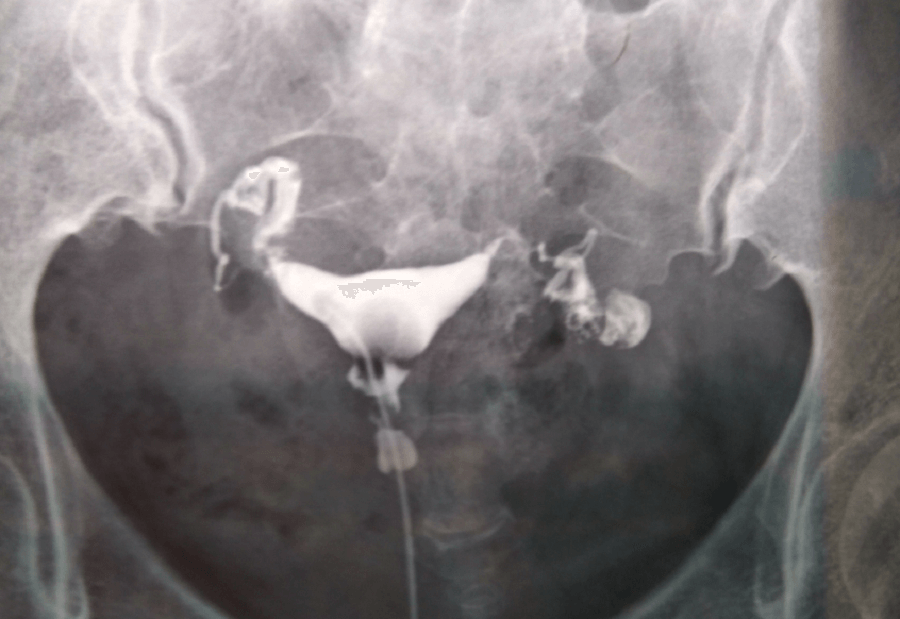

通常有輸卵管問題的患者要根據實際情況判斷能否直接試管助孕,比如做過計劃生育結紮手術、輸卵管嚴重梗阻和積水、粘連炎症等輸卵管問題很嚴重的患者,需要在專業醫生的指導下通過相關手術治療後再做試管助孕。一般是經腹腔鏡各方面手術治療或者通過中醫藥物治療後,輸卵管仍然堵塞,方可做試管嬰兒。本人備孕歷程分享本人2011年4月在安醫附院做造影后,一邊輸卵管上舉,一邊傘端炎症,做了一個療程的灌腸後,醫生建議監測排卵...